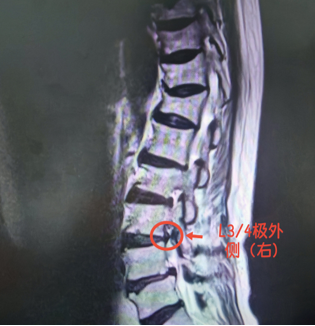

看着父亲日渐消瘦,儿子经人推荐,带他来到石门县人民医院脊柱外科求治。副主任医师王强仔细检查后,盯着 CT 片子皱起眉头:“您的突出物‘跑偏’了,躲进了神经根出门的‘门缝’里!”

原来,陈大爷得的是 “极外侧型腰椎间盘突出”—— 这是一种仅占腰椎间盘突出症 4.1%~11%、却极易被漏诊的特殊类型。

检查易 “漏网”:常规 CT 平扫横断面上,椎管内无明显异常,需通过薄层 CT 精确扫描椎间孔内及外侧区,才能发现低密度软组织团块;MRI (核磁共振)上则可见椎间孔内神经根显影不清、受压迫。